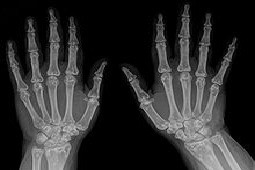

Zdjęcia rentgenowskie stawów rąk wykazały ostatnio zmiany odpowiadające III/IV okresowi RZS, szczególnie w stawach nadgarstkowych, i towarzyszące im zagęszczenia tkanki kostnej typowe dla plamistej postaci OPK (ryc. 2a, b). Zdjęcia stawów stóp i stawów skokowych uwidoczniły zmiany związane z OPK (ryc. 3a–d).